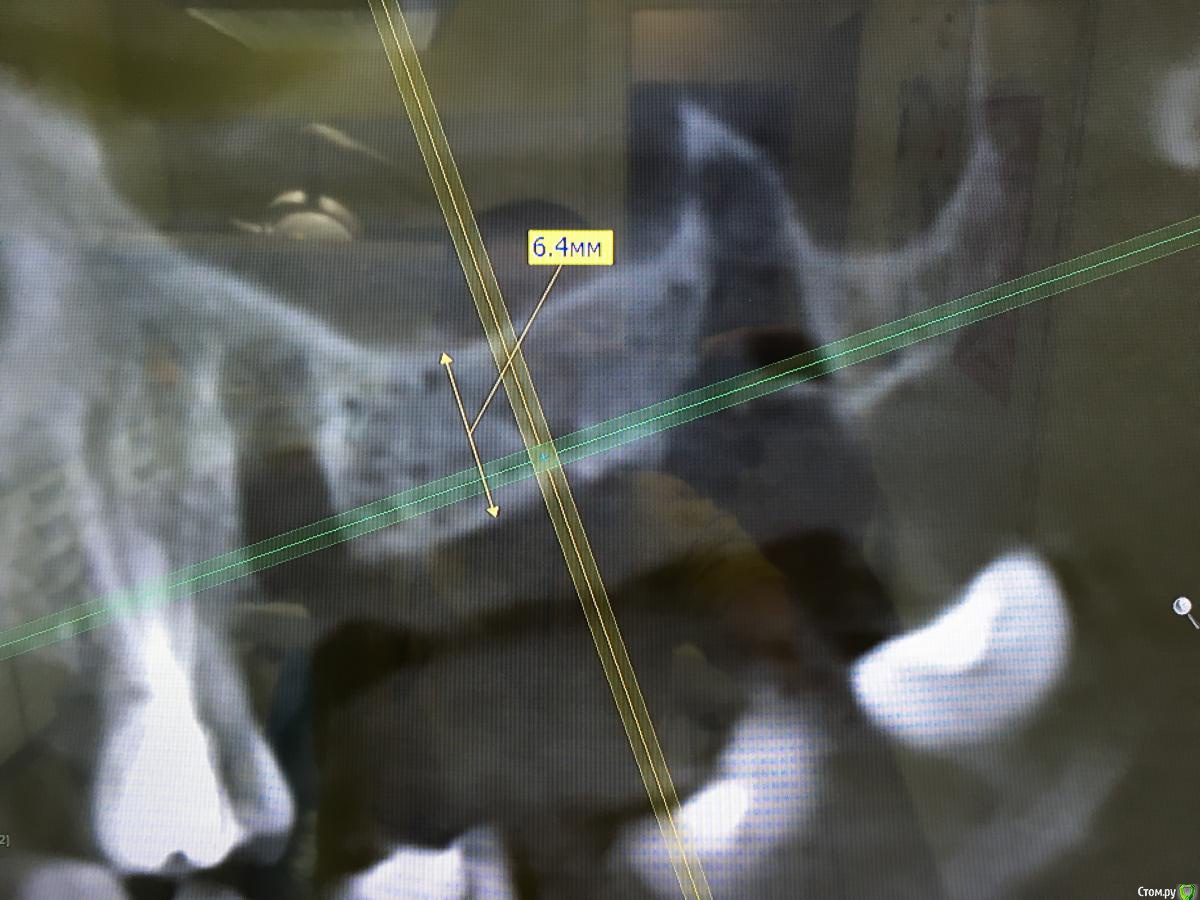

mann Опубликовано 20 февраля, 2017 Автор Поделиться Опубликовано 20 февраля, 2017 Добрый вечер! Нет таких имплантов,чтобы сюда закрутить?без синуслифтинга Ссылка на комментарий

karasov Опубликовано 20 февраля, 2017 Поделиться Опубликовано 20 февраля, 2017 (изменено) Добрый вечер! Нет таких имплантов,чтобы сюда закрутить?без синуслифтингаbicon крути любой прям в синус. Или подожди пока лунки удаленных зубов немного заживут и крути в них Изменено 20 февраля, 2017 пользователем karasov Ссылка на комментарий

Bier Опубликовано 20 февраля, 2017 Поделиться Опубликовано 20 февраля, 2017 Добрый вечер! Нет таких имплантов,чтобы сюда закрутить?без синуслифтингаесть астра 6.0 1 Ссылка на комментарий